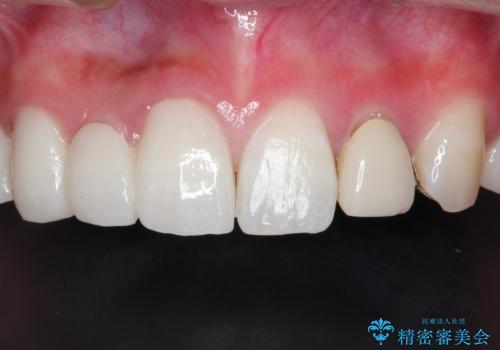

- 保険治療で装着されたかぶせ物と詰め物を変更したいとのことで来院されました。

自然なオールセラミックへ変更することとなりました。

金属を使わないセラミックへ変更することで、自然な見た目になるとともに、ぴったりとした精度の高いかぶせ物を装着することができました。